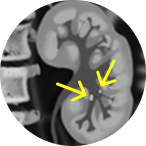

Jelmyto® (mitomycin) for pyelocalyceal solution is indicated for the treatment of adult patients with low-grade Upper Tract Urothelial Cancer (LG-UTUC).

This portrays real-world scenarios in which JELMYTO was used in a diverse range of tumor types. UroGen's Olympus trial studied patients with treatment-naïve or recurrent LG-UTUC with ≥1 measurable papillary tumor 5 to ≤15 mm located above the ureteropelvic junction (tumor debulking was permitted prior to study enrollment for tumors >15 mm).1 For additional inclusion and exclusion criteria, please see the Olympus trial study design.